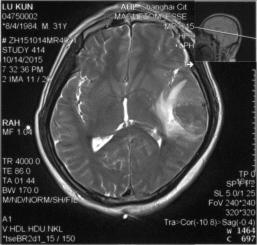

脑MRI:左侧横窦条索状高信号,左颞叶脑出血,见图3&6、7、8

图3